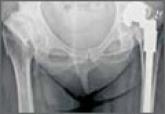

Total Hip and Knee Replacement in a Patient with Arthrogryposis Multiplex Congenita

Arthrogryposis multiplex congenita (AMC) is a complex disorder that leads to joint stiffness and deformities in 2 or more joints in afflicted...